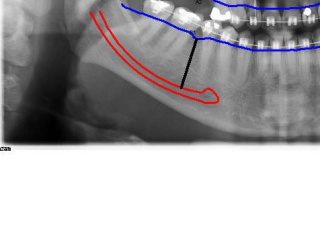

Enxerto de seio maxilar